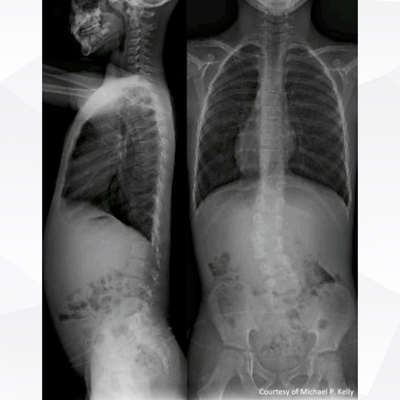

Click on an image below to view more info.